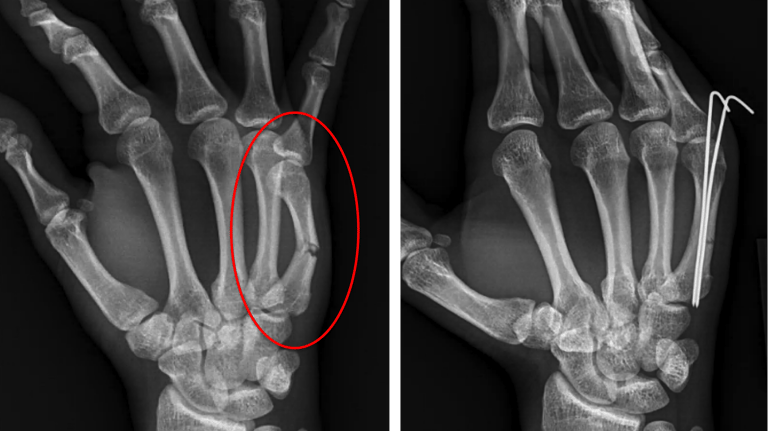

Hand & Wrist Fracture Management

Metacarpal & Phalangeal Fractures